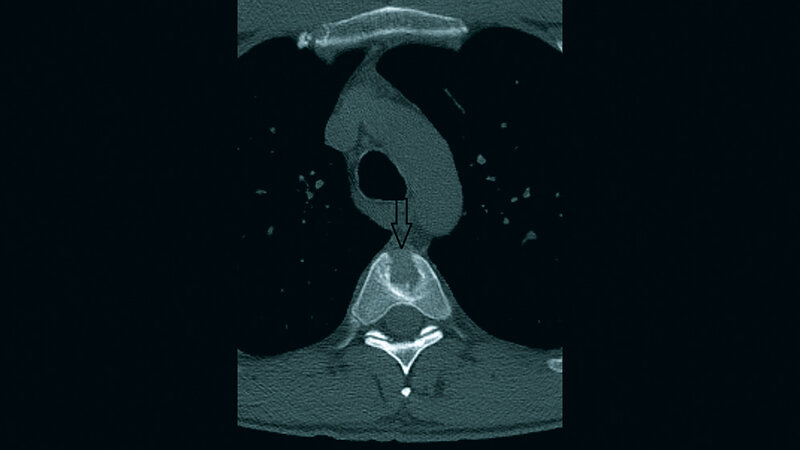

Der Schmetterlingswirbel ist eine seltene angeborene Fehlbildung der Wirbelsäule. Er wird meist als Nebenbefund gefunden und ist asymptomatisch.

Butterfly vertebra is an uncommon congenital spinal anomaly. It is considered to be incidental and usually asymptomatic.